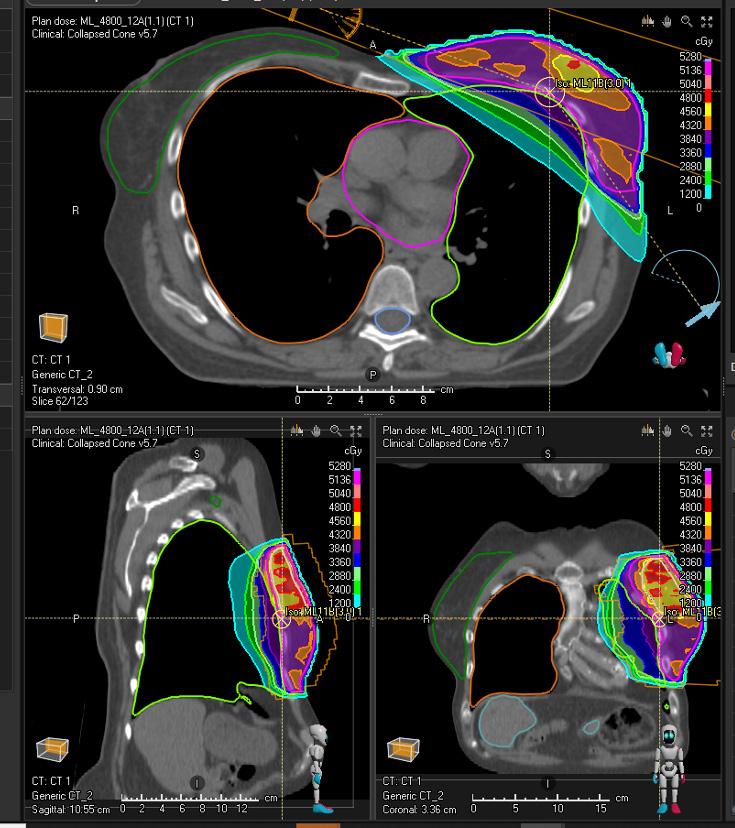

Validation patient example

Treatment site Breast

Modality Photons

Treatment technique Validated for VMAT

Primary prescription [cGy] 4800

Number of fractions 16

Dose per fraction [cGy] 300

MODEL PROTOCOL

ROI Clinical goals

PTV High At least 4560 cGy dose at 98.0 % volume

PTV High At most 4944 cGy dose at 2.0 % volume

PTV High At least 96.0 % volume at 4560 cGy dose

PTV High At most 1.0 % volume at 5040 cGy dose

PTV Low At least 3940 cGy dose at 98.0 % volume

PTV Low-PTV High At most 4800 cGy dose at 1.0 % volume

PTV Low At least 95.0 % volume at 4028 cGy dose

PTV Low-PTV High At most 15.0 % volume at 4452 cGy dose

PTV High At least a conformity index of 0.8 at 4560 cGy isodose

PTV High At least a homogeneity index of 0.9 at 98.0 % volume

PTV Low At least a conformity index of 0.85 at 4028 cGy isodose

PTV Low At least a homogeneity index of 0.8 at 95.0 % volume

Lung L At most 25.0 % volume at 500 cGy dose

Lung L At most 15.0 % volume at 1000 cGy dose

Lung L At most 7.0% volume at 2000 cGy dose

Lung L At most 1.0 % volume at 4000 cGy dose

Lung L At most 600 cGy average dose

Lung R At most 100 cGy average dose

Lung R At most 400 cGy dose at 1.0 % volume

Heart At most 150 cGy average dose

Heart At most 500 cGy dose at 1.0 % volume

Breast R At most 200 cGy average dose

Breast R At most 700 cGy dose at 1.0 % volume

A Coronary L At most 200 cGy dose at 1.0 % volume

Humerus L At most 200 cGy average dose

Brachial Plexus L At most 4240 cGy dose at 0.0 % volume

Liver At most 200 cGy dose at 0.0 % volume

Spinal Canal At most 200 cGy dose at 0.0 % volume